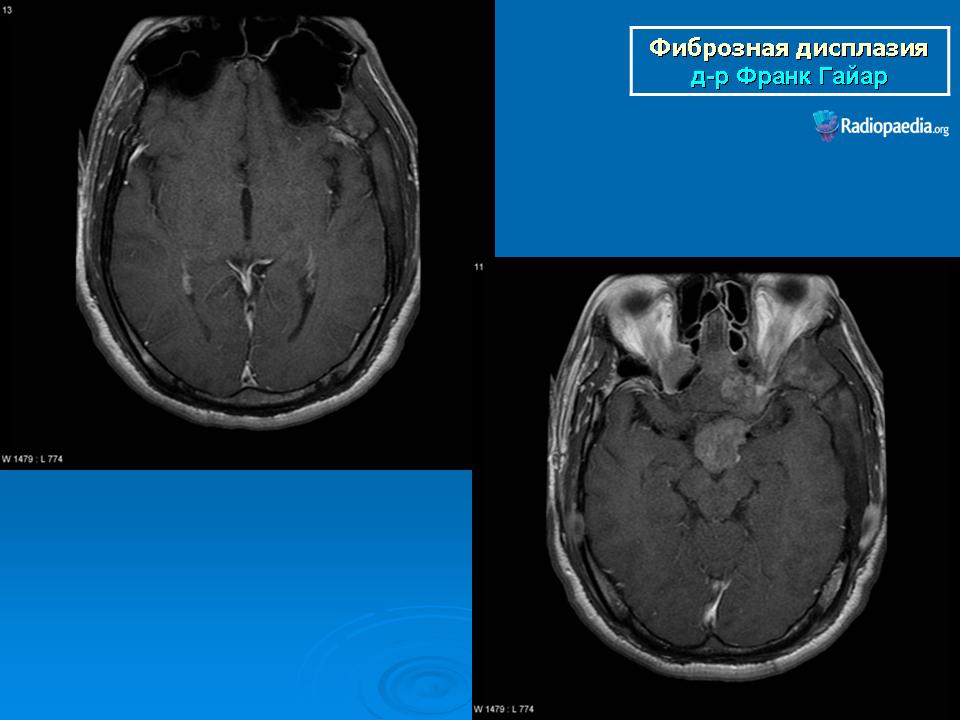

Фиброзная дисплазия

Для фиброзной остеодисплазии, или болезни Брайцева-Лихтенштейна, характерно нарушение костеобразующей функции мезенхимы, проявляющееся в одной или нескольких костях, что ведет к их деформации и образованию в них очагов разрежения, обычно отграниченных от здоровой ткани кости склеротической каймой. Объем пораженной кости при этом может быть увеличен. Чаще поражаются трубчатые кости, но характерные изменения могут отмечаться и в костях черепа. В таких случаях возможны облитерация придаточных полостей носа, деформация глазниц, сужение отверстий в основании мозгового черепа и в лицевом черепе, ведущее к нарушению функции проходящих через них нервов и сосудов. Заболевание, возможно, наследственное, проявляется с детских лет. Описал в I927 г. отечественный хирург В.Р. Брайцев (1878-1964), несколько позже - американский патологоанатом L. Lichtenstein (1906-1977).

Полиостотическая фиброзная дисплазия у пациента с синдромом Маккьюн - Олбрайта.